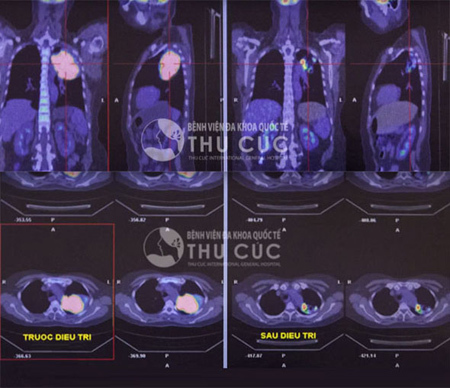

![]() |

| Kết quả điều trị của 1 bệnh nhân ung thư phổi sau 4 chu kỳ truyền hóa chất. Khối u gần như biến mất. |